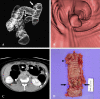

Purpose: We sought to evaluate the clinical usefulness of CT colonography (CTC) after incomplete conventional colonoscopy (CC) for occlusive colorectal cancer (CRC) according to the tumor location.

Materials and methods: Seventy-five patients with occlusive CRC underwent subsequent CTC immediately after incomplete CC. Fifty-nine patients had distal CRC and 16 had proximal colon cancer. Experienced radiologists prospectively analyzed the location, length, and TNM staging of the main tumor. The colorectal polyps in the remaining colorectum and additional extraluminal findings were also recorded. Sixty-seven patients underwent colorectal resection. We retrospectively analyzed the surgical outcome and correlated CTC and CC findings.

Results: The overall accuracies of tumor staging were: T staging, 86%; N staging (nodal positivity), 70% (80%); and intra-abdominal M staging, 94%. Additional colonic polyps were found in 23 patients. Six synchronous carcinomas were detected (9%); three in the proximal colon and three in the distal colon of occlusion. Clinically significant localization errors at CC were noted in 8 patients (12%, 5 proximal colon cancers and 3 distal CRCs) and were corrected by CTC. After CTC, the surgeons modified the initial surgical plan in 11 cases (16%).

Conclusion: In occlusive CRC, CTC is not only useful in the evaluation of the proximal bowel, but can also provide surgeons with accurate information about staging and tumor localization. CTC is recommended when endoscopists encounter occlusive CRC, regardless of tumor location.